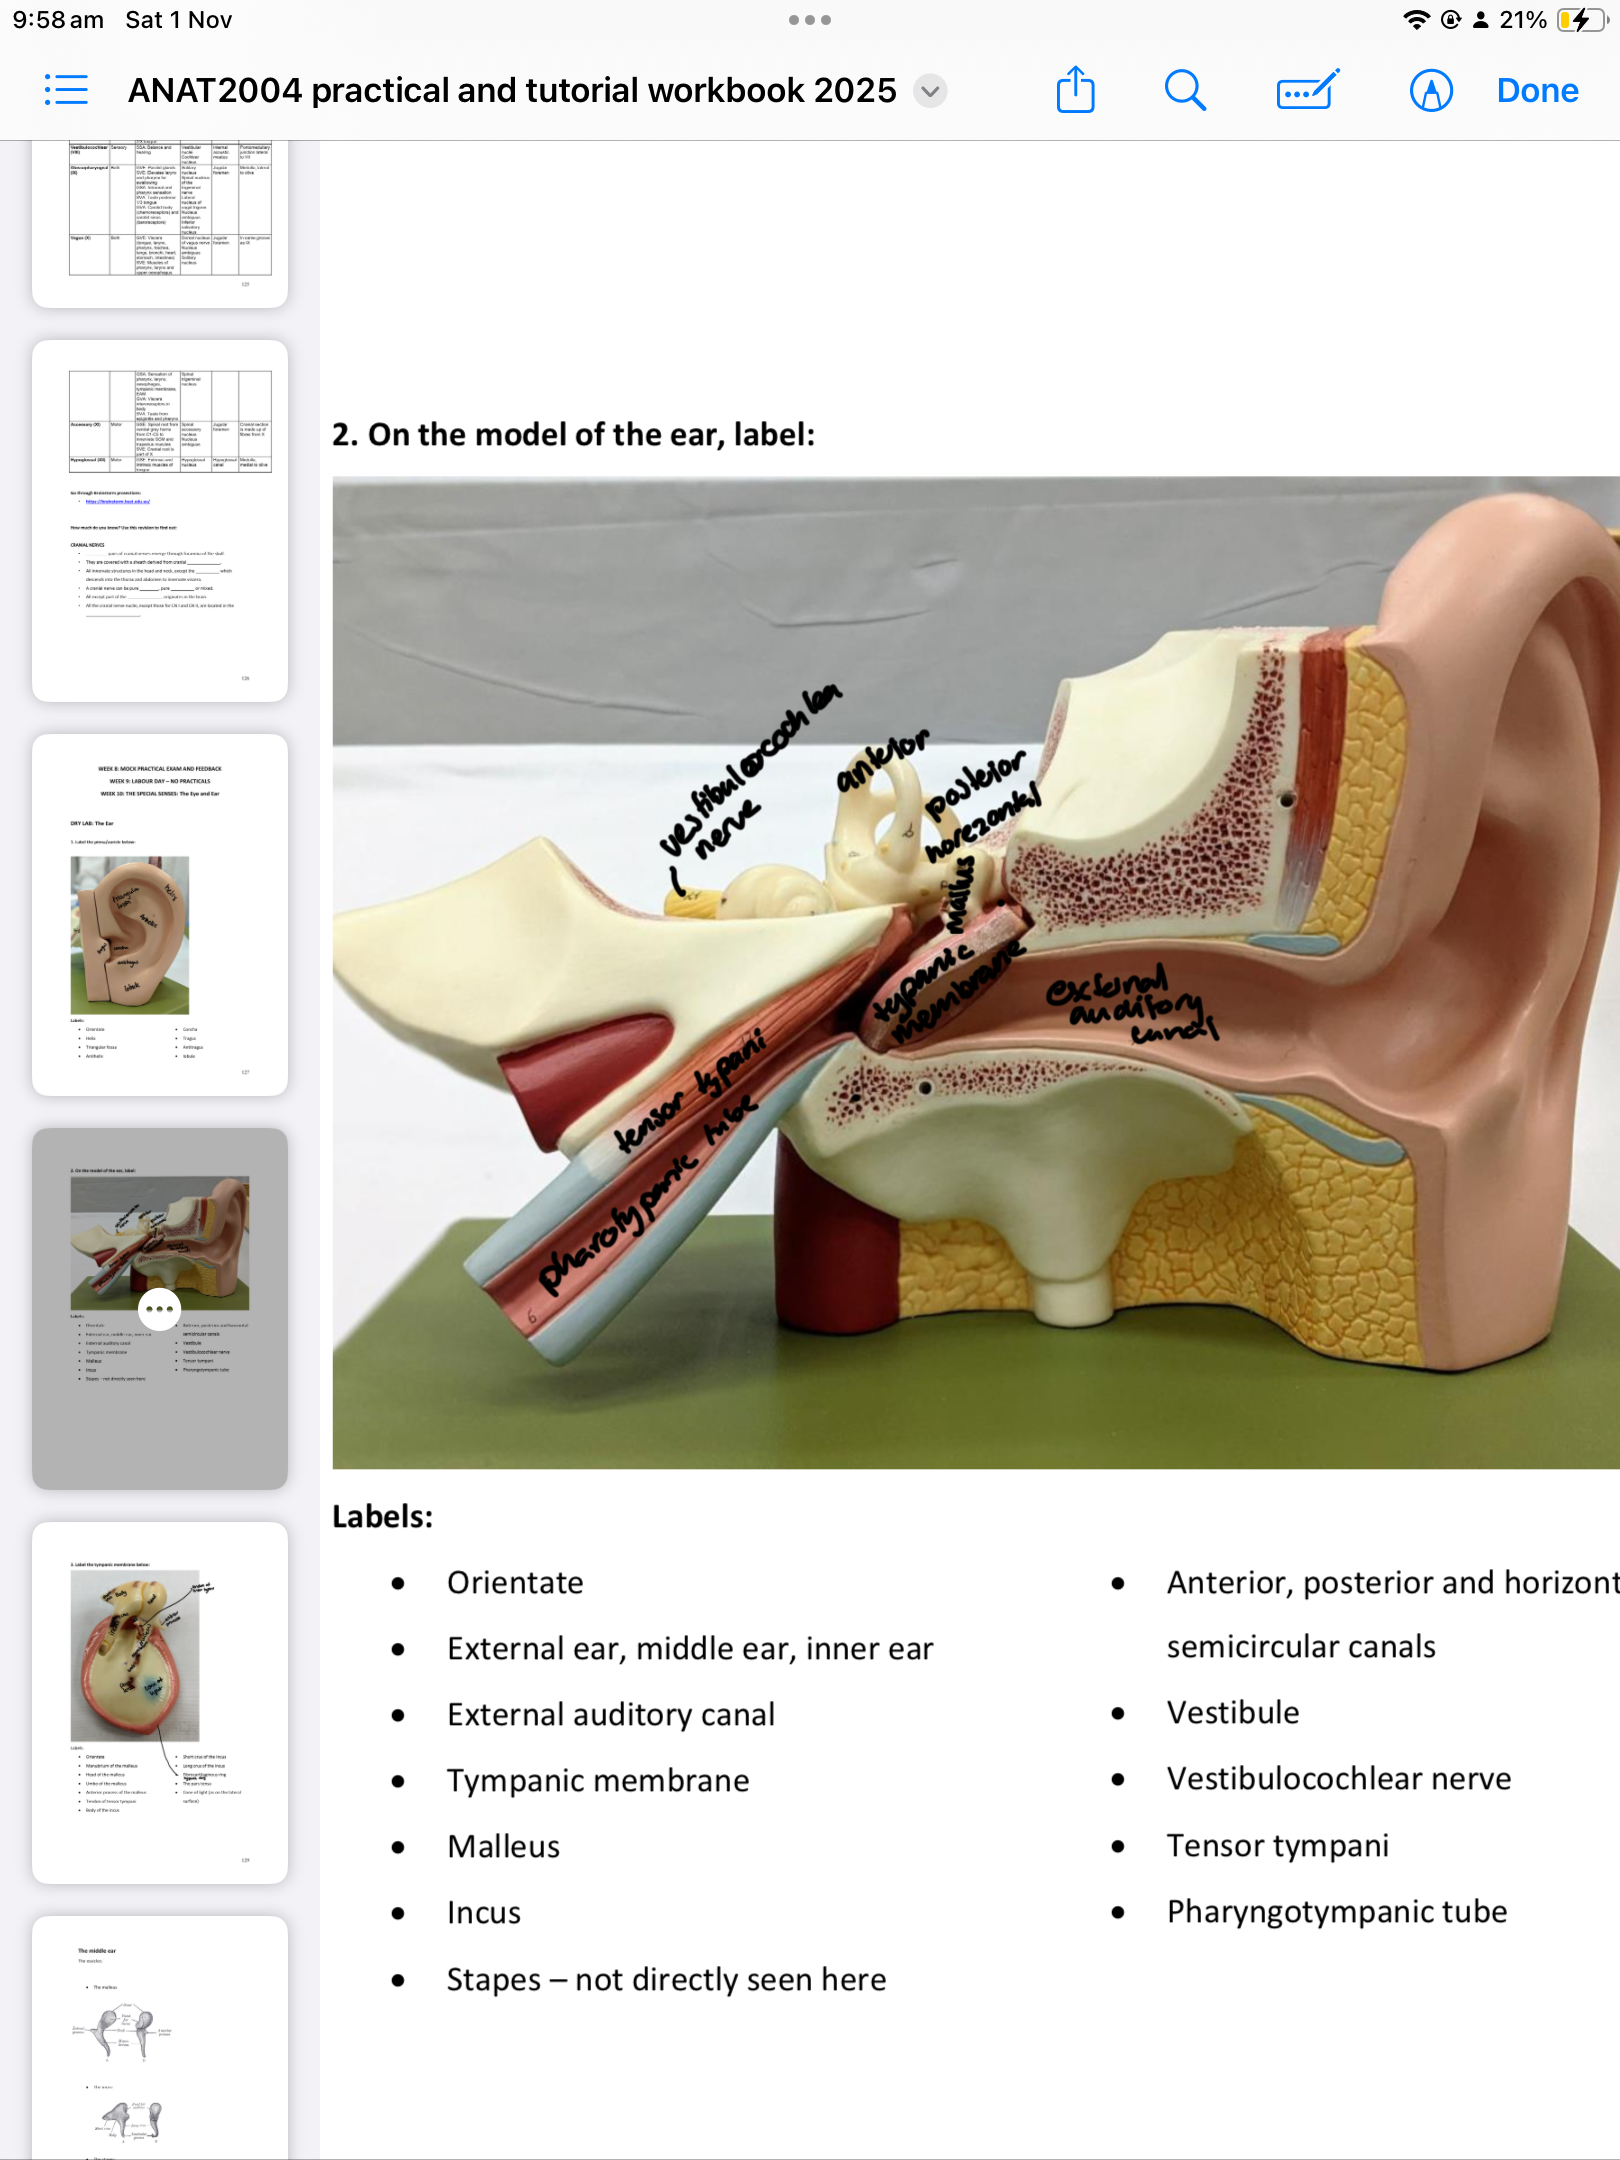

The Middle Ear

External auditory canal

Tympanic membrane

Malleus & Incus

Horizontal semicircular canals

Vestibule

Vestibulocochlear nerve

Tensor tympani

Pharyngotympanic tube